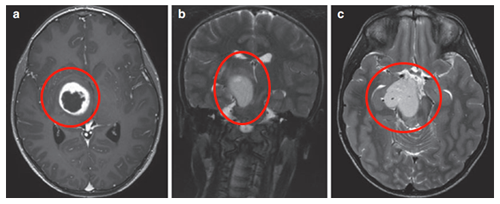

3歲患兒因嘔吐和巨腦畸形就醫(yī)。CT及MRI顯示右側(cè)丘腦病變伴鈣化及后三腦室梗阻,引起腦積水(圖1)。

在8歲、11歲和13歲時,James T.Rutka教授成功地利用第三腦室內(nèi)窺鏡切開術(shù)治療腦積水(圖2為系列影像),且影像顯示腫瘤增大和多發(fā)腫瘤囊腫(箭頭狀),并逐漸出現(xiàn)左上肢震顫。

患兒在13歲時進行了神經(jīng)導航和超聲引導下的活檢,證實為腦瘤為WHO I級,毛細胞星形細胞瘤。腫瘤囊腫持續(xù)擴大(圖3),患兒發(fā)展為急性偏癱。

示同側(cè)內(nèi)囊(負責人體肢體運動)前外側(cè)移位(箭頭)(圖4)。超聲引導下將Ommaya導管和儲層插入腫瘤囊性部分。

術(shù)后MRI顯示囊性占位接觸,腦室慢慢恢復正常。(圖5j)四個月后,由于患兒的偏癱沒有改善,Rutka教授為其行經(jīng)胼胝體半球間入路及腫瘤次全切除術(shù)。

術(shù)后影像(圖5),術(shù)后患兒偏癱改善,患兒生長和智力發(fā)育正常,近期隨訪顯示腦瘤未復發(fā)。免疫組化檢測RAFV600E突變免疫無陽性,H3K27M陰性。

(圖6a、b)軸位MRI造影劑及冠狀面T2-WI顯示一個環(huán)形增強的右側(cè)丘腦結(jié)節(jié)腫瘤。

腫瘤累及內(nèi)側(cè)顳結(jié)構(gòu)(圖6c),Rutka教授考慮根據(jù)其病情進展制定綜合治療方案,先行經(jīng)顳中回經(jīng)腦室入路次全切除腫瘤,組織學為WHO I級毛細胞星形細胞瘤,BRAF重復融合狀態(tài)為陰性。免疫組化檢測BRAF V600E、H3K27M陰性?;驕y試證實了NF1基因的變異。術(shù)后嚴密隨訪患兒術(shù)后情況。

(圖7)六個月后的影像顯示丘腦部分切除和中腦的小腫瘤殘留,因此,Rutka教授根據(jù)其病情發(fā)展量身定制輔助治療計劃,患兒對放療反應良好。

患者是一名6歲男童,癥狀為頭痛、間歇性左上肢震顫。MRI(FLAIR序列)顯示一個兩側(cè)丘腦腫瘤,右比左大,尾狀核的右頭部也參與其中。腦室輕度增大,膈膜水腫,腫瘤內(nèi)部囊腫。因此,Rutka教授為其先行左額部內(nèi)窺鏡活檢和鼻中隔造瘺術(shù),再行左枕腦室-腹腔分流術(shù)。